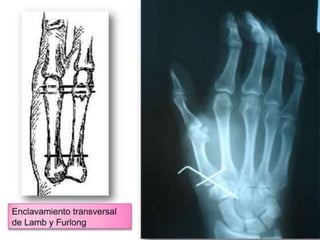

Método de reducción:

   Para reducir la ”luxación” de Bennett

se utiliza la reducción cerrada con las

técnica de Iselin, Wagner, o Wiggins.

Su tratamiento puede ser Cxo o Qxo

Los métodos de tratamiento de las fracturas

de la base del pulgar son numerosos e

incluso podríamos hablar de ingeniosos en

algunas ocasiones, yendo desde el simple

tratamiento funcional con movilización

inmediata y sin reducción ni contención de

ninguna clase propuesto por LESTER y

BLUM (1941), hasta la reducción quirúrgica

y osteosíntesis.

Es una fractura fácil de reducir pero muy

difícil de contener. Se puede intentar una

reducción ortopédica con un yeso, y si no

se mantiene la reducción realizar un

tratamiento quirúrgico que depende del

tamaño del fragmento. Si el fragmento es

grande, síntesis con tornillo por vía dorsal

y si es pequeño, reducción cerrada y

estabilización.